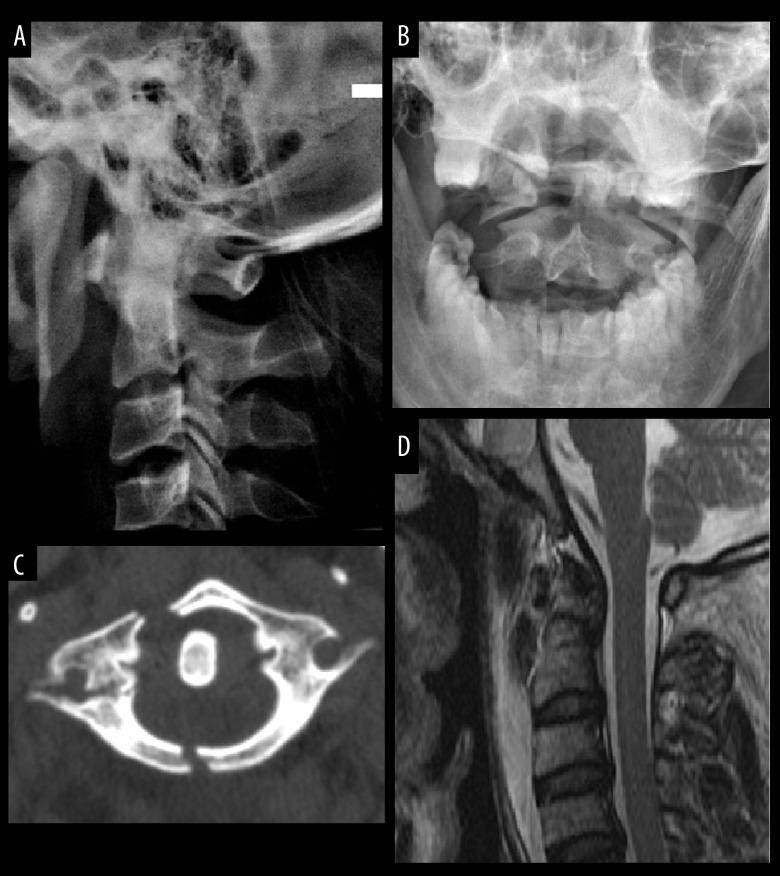

BACKGROUND Although most unstable C1 fractures can be effectively treated either by conservative treatment with external immobilization or by surgical procedure of C1-ring osteosynthesis, those fractures involving the lateral mass are likely to lead to traumatic arthritis and persistent neck pain. Specific reports of treatment of unstable C1 fractures involving the lateral mass are still scarce. We therefore present this report to evaluate the effectiveness of posterior C1-C2 screw-rod fixation and fusion for unstable C1 fractures involving the lateral mass. MATERIAL AND METHODS From June 2009 to June 2016 in our hospital, 16 cases were diagnosed with C1 fractures involving the lateral mass and treated by posterior C1-C2 screw-rod fixation and fusion from June 2009 to June 2016. The patients' clinical data were retrospectively analyzed. Preoperative and postoperative images were taken to evaluate cervical sequence, location of screws, and bone fusion. Neurological status and neck pain levels were evaluated clinically on follow-up. RESULTS All patients underwent surgery successfully. The mean follow-up duration was 15.3±4.9 months (range 9-24 months). All patients obtained satisfying clinical outcomes with good neck pain alleviation, appropriate screw placement, and reliable bone fusion. None of the patients developed vascular or neurological complications during the operation or follow-up. CONCLUSIONS Posterior C1-C2 screw-rod fixation and fusion is an effective management for unstable C1 fractures involving the lateral mass. This operation can provide reliable stabilization and satisfactory bone fusion.

虽然大多数不稳定的 C1 骨折可以通过保守治疗(外部固定)或 C1 环骨合成术进行有效治疗,但涉及侧块的骨折可能导致创伤性关节炎和持续的颈部疼痛。涉及侧块的不稳定 C1 骨折的具体治疗报告仍然很少。因此,我们报告了评估后路 C1-C2 螺钉-棒固定和融合治疗涉及侧块的不稳定 C1 骨折的疗效。

在我们医院,自 2009 年 6 月至 2016 年 6 月,16 例诊断为涉及侧块的 C1 骨折患者,采用后路 C1-C2 螺钉-棒固定和融合治疗。回顾性分析患者的临床资料。拍摄术前和术后图像以评估颈椎序列、螺钉位置和骨融合情况。在随访时对神经状态和颈部疼痛水平进行临床评估。

所有患者均成功接受手术。平均随访时间为 15.3±4.9 个月(范围 9-24 个月)。所有患者均获得了满意的临床结果,颈痛缓解良好,螺钉放置适当,骨融合可靠。在手术和随访期间,没有患者发生血管或神经并发症。